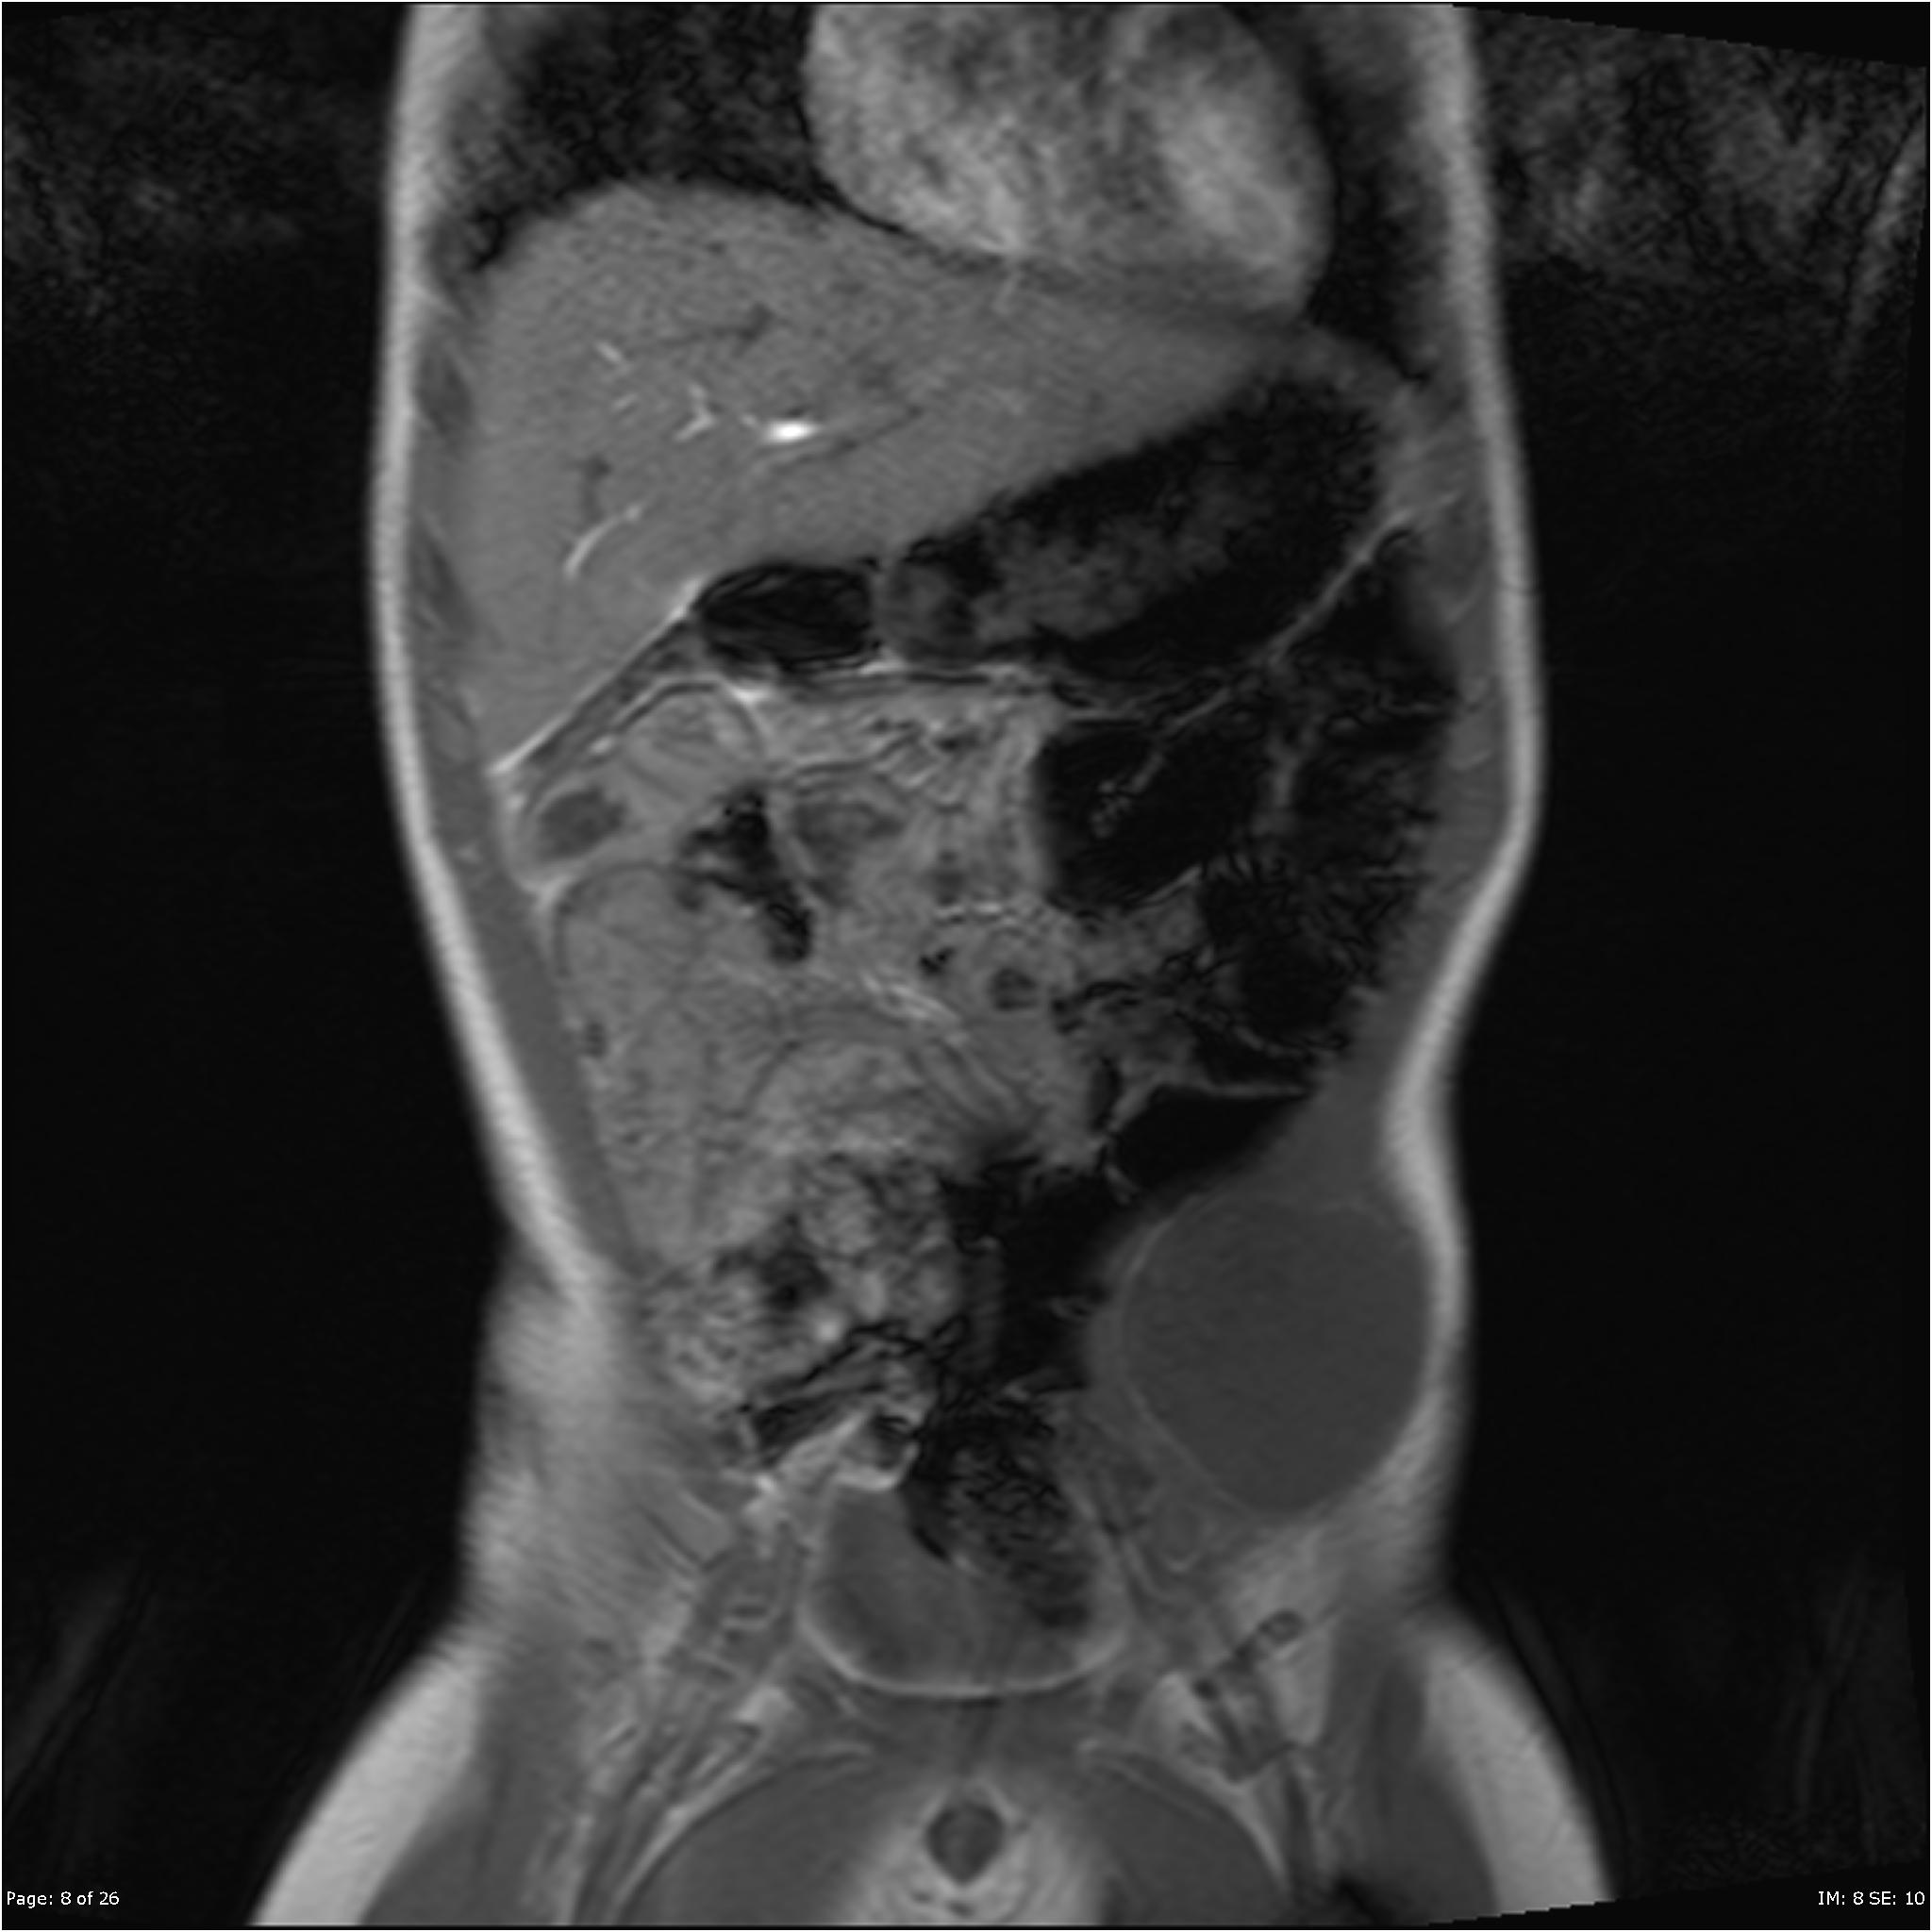

Case example of a patient with a retroperitoneal A frail